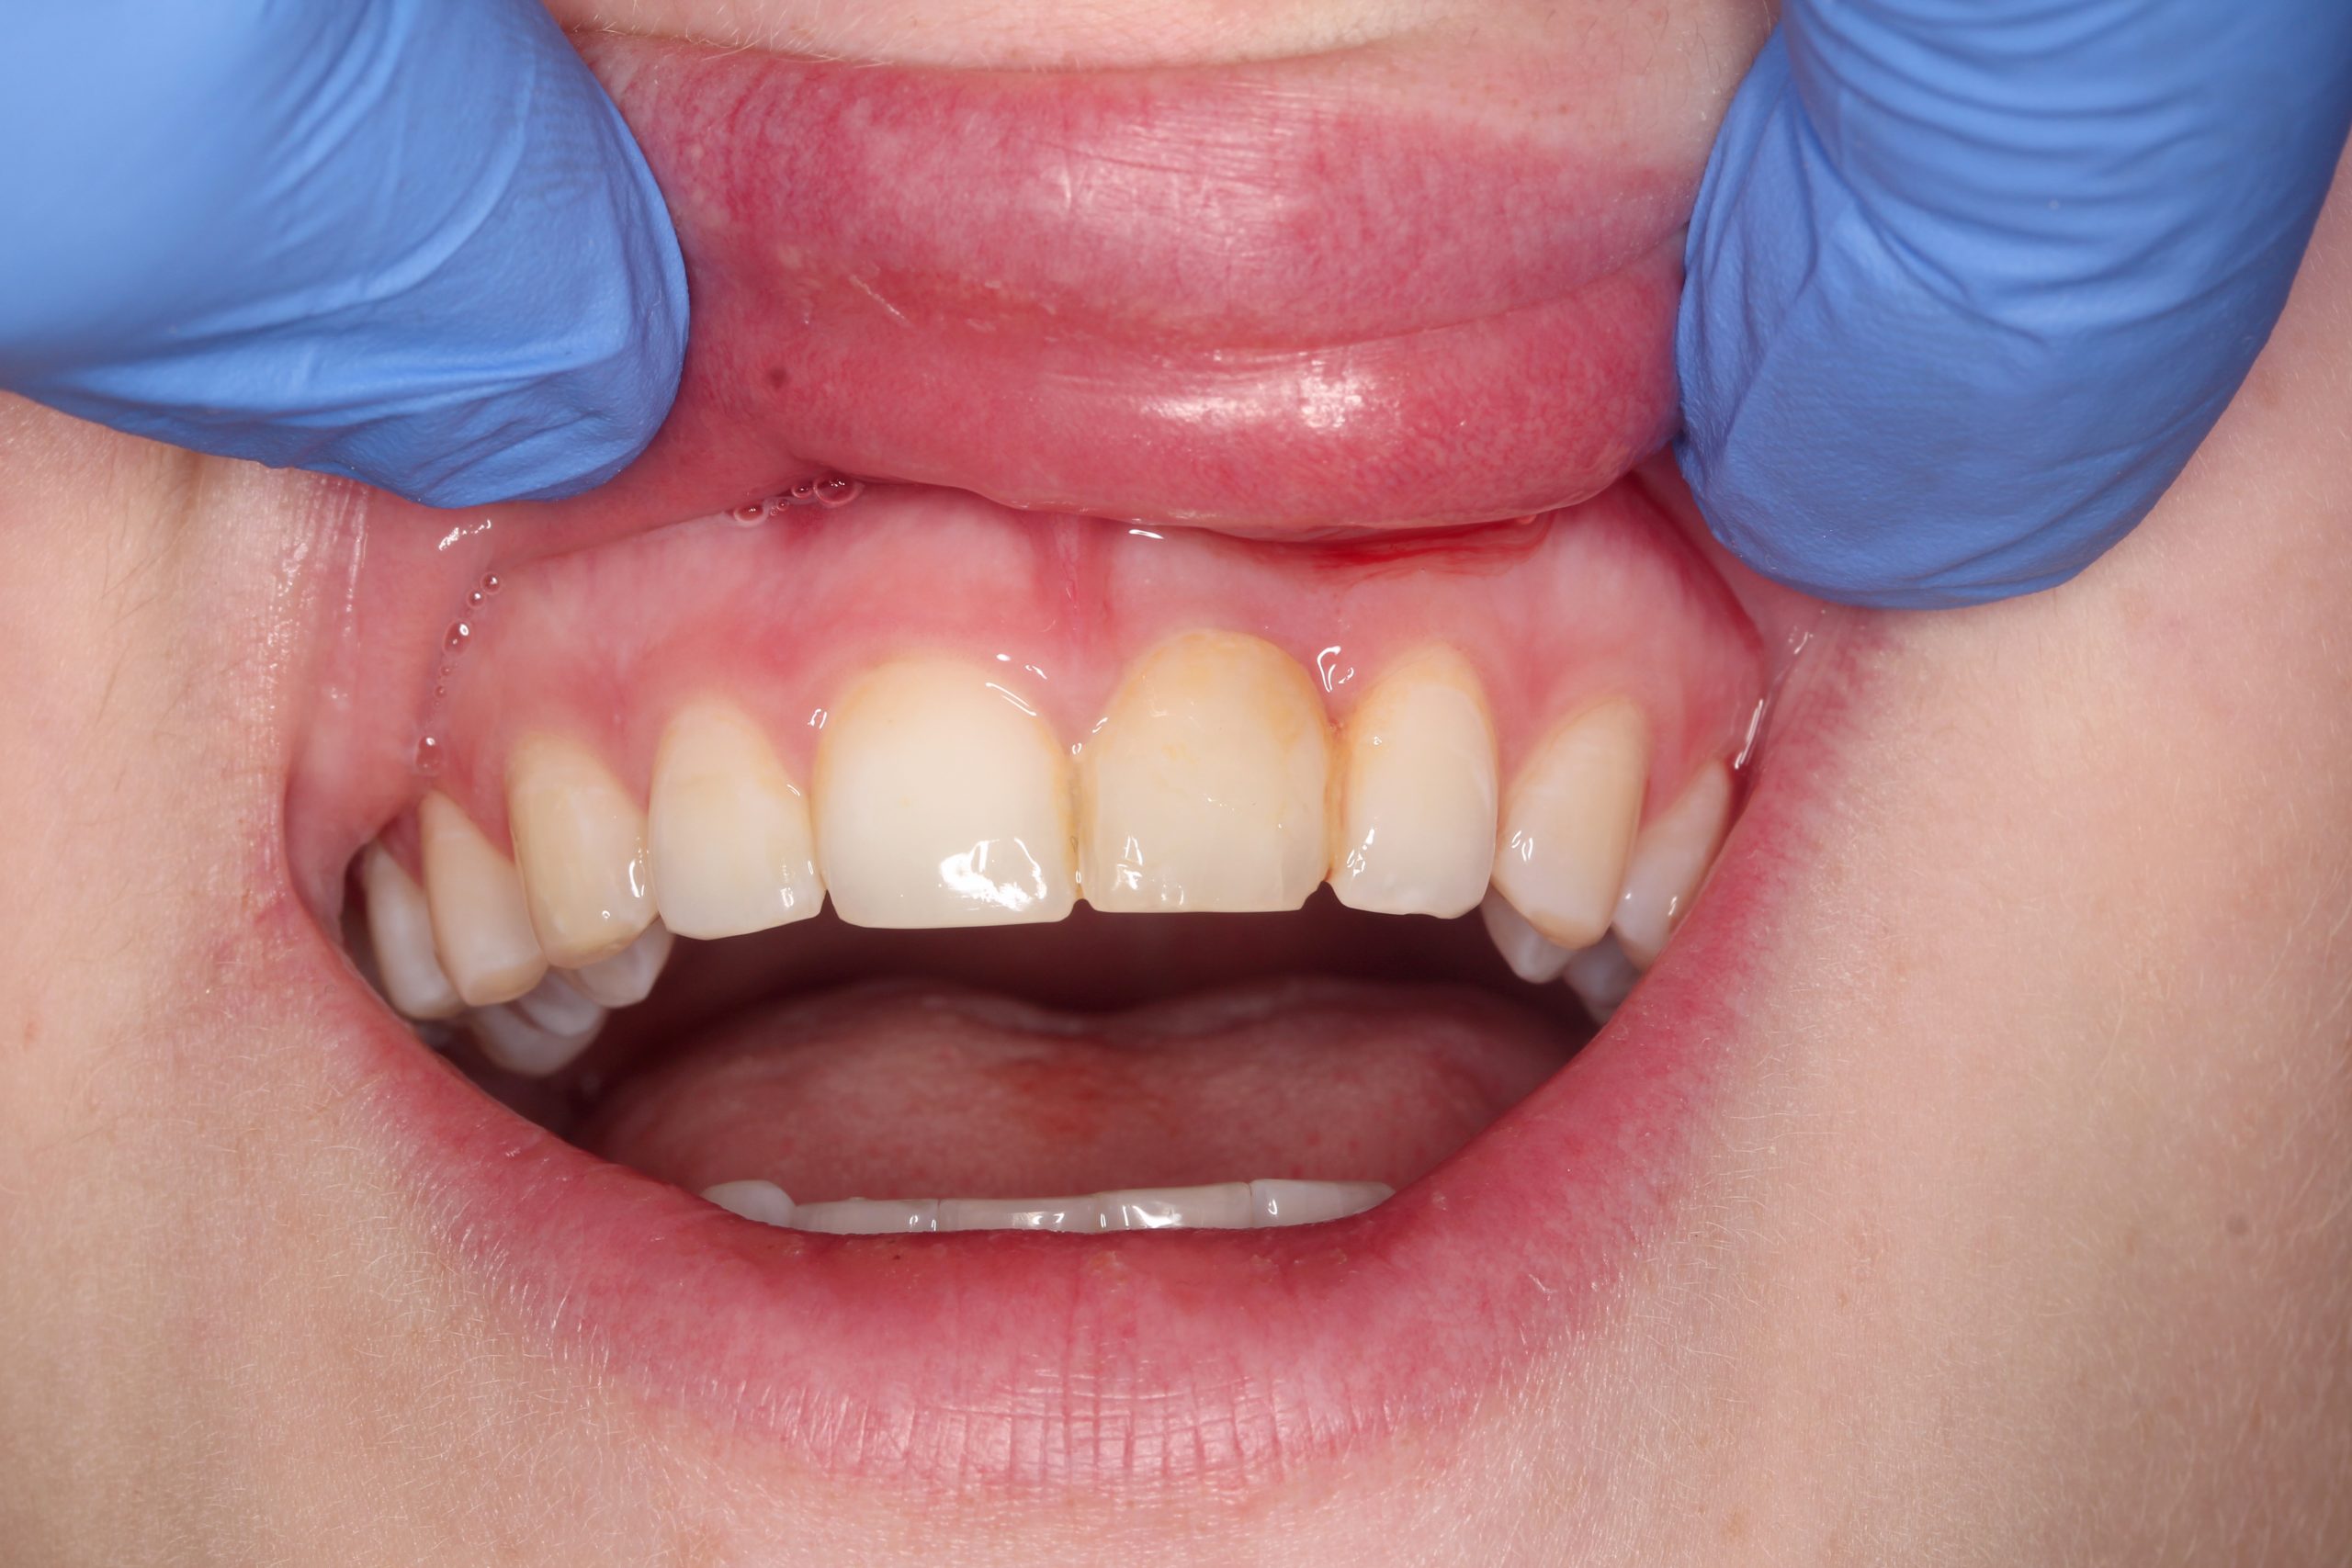

Bei dem Follow-up nach einem Monat sind keine Probleme aufgetreten. Der provisorische Zahnersatz war in das umgebende Gewebe integriert und die Ästhetik des Weichgewebes ist erhalten worden.

Vier Monate nach der Implantation und der Sofortbelastung wurde die provisorische Krone entfernt. Eine vollkeramische Krone wurde im Labor angefertigt.

Das Lächeln der Patientin beim Recall nach drei Jahren. Durch minimalinvasive chirurgische Eingriffe und die Schonung des umliegenden Gewebes konnte ein bestmögliches ästhetisches und gleichwohl funktionelles Ergebnis erzielt werden.